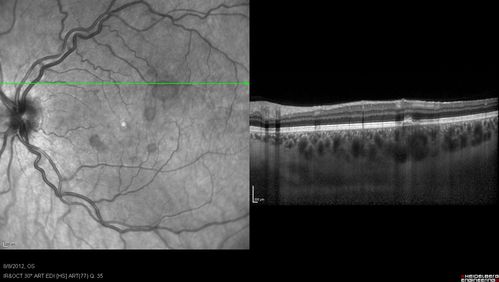

Punctate Inner Choroidopathy - PIC and Choroidal Neovascular Membrane - Right Eye - SD OCT

34-year-old woman with a change in vision in the right eye about eight days ago.  Her vision was hazy and she saw waviness in the vision.  She does have a history of aches and pains and she was diagnosed with Sjogren’s and 2 months ago she had some fevers and some sinus drainage and that went on for about two months.  She is a moderate myope.    OD 20/25, OS 20/20.